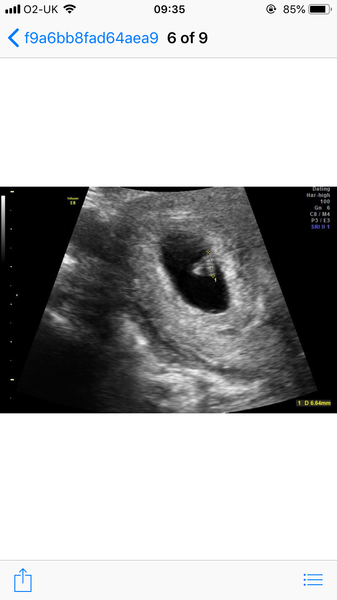

Erin4000 · 12/01/2019 09:35

Here is a pic! Not much to see really but 😀 x

@Erin4000 how far along are you? I've got my 2nd scan on Tuesday and hoping to see more than a sac. I'll be 6 wks 3 days.

@waiting4arainbow I was 6+4 on scan day but measured at 6+3 and they saw heartbeat x hope your scan goes well xx